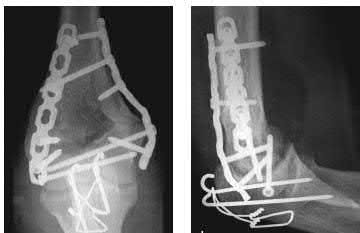

A 28-year-old male sustains a severe hyper-dorsiflexion injury to his ankle in a motor vehicle accident, resulting in a Hawkins Type III talar neck fracture. Which of the following arteries provides the predominant blood supply to the body of the talus, placing it at significant risk for avascular necrosis in this injury?

Correct Answer: Artery of the tarsal canal

Explanation:

The artery of the tarsal canal, which is a branch of the posterior tibial artery, provides the dominant blood supply to the talar body. In a Hawkins Type III fracture (talar neck fracture with subtalar and tibiotalar dislocation), the blood supply from the artery of the tarsal canal, the artery of the sinus tarsi, and capsular vessels are disrupted, leading to an avascular necrosis (AVN) rate approaching 100%.